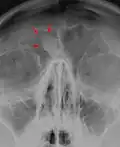

Osteoma represents the most common benign neoplasm of the nose and paranasal sinuses. The cause of osteomas is uncertain, but commonly accepted theories propose embryologic, traumatic, or infectious causes. They are present in Gardner's syndrome.

Larger craniofacial osteomas may cause facial pain, headache, and infection due to obstructed nasofrontal ducts. Often, craniofacial osteoma presents itself through ocular signs and symptoms (such as proptosis).[2]